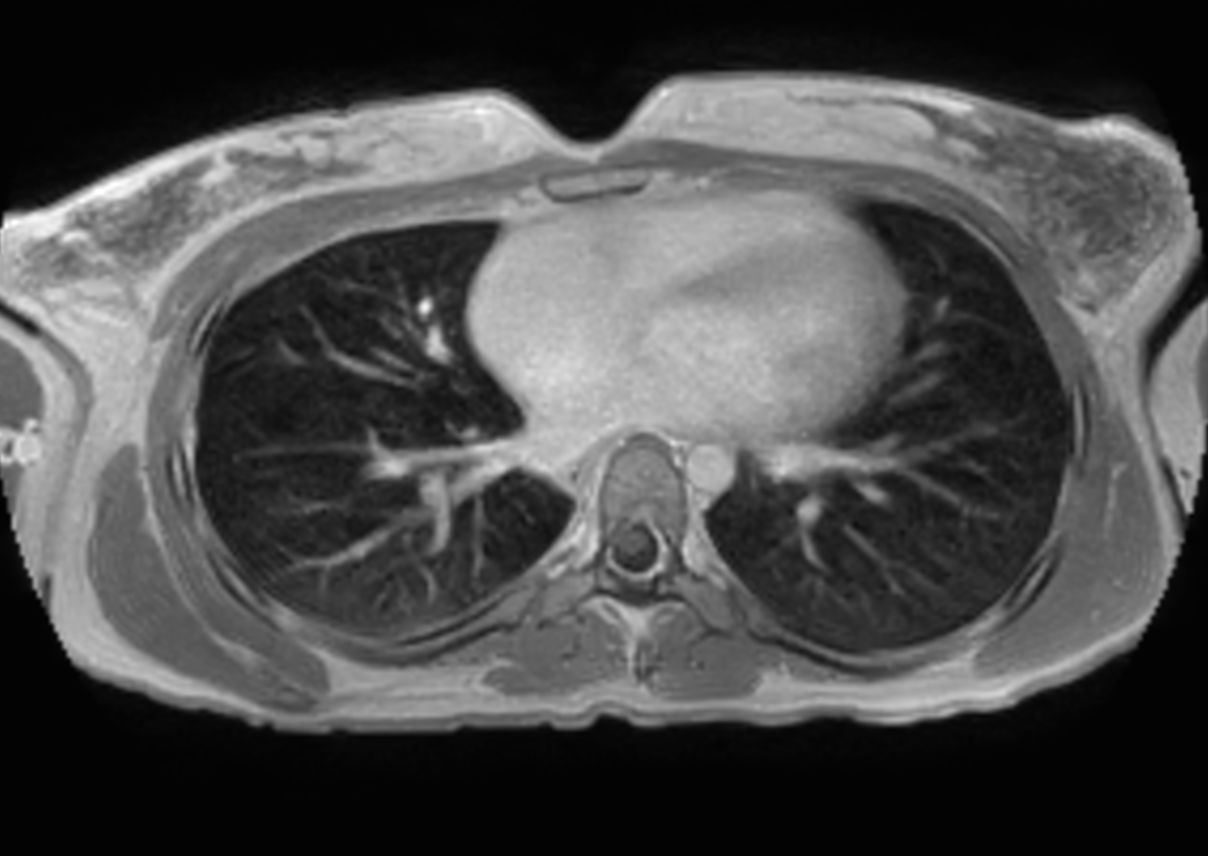

T1w mDIXON XD (Out Phase)